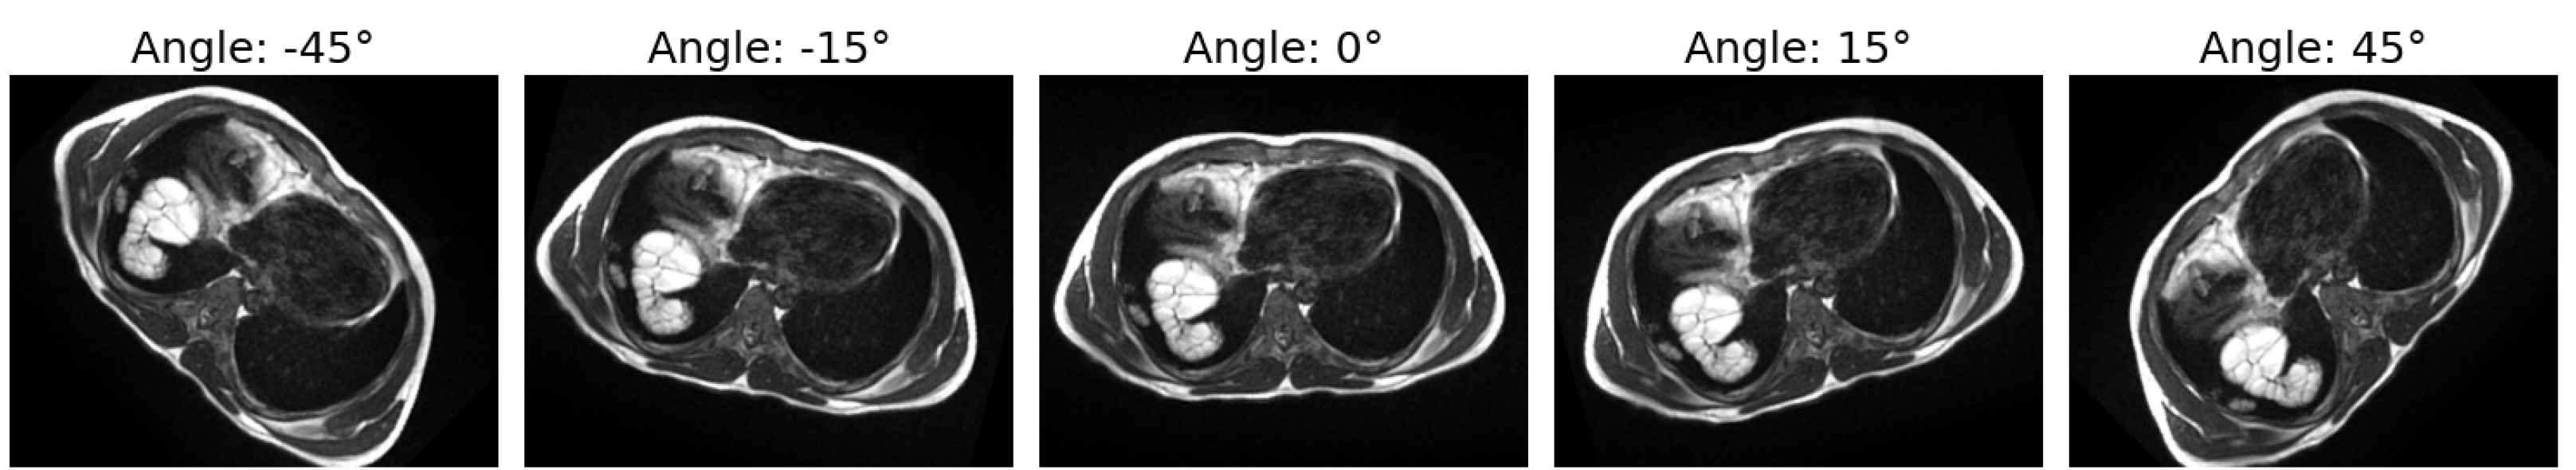

To augment MRI images, we specifically applied rotation. It is crucial to avoid excessive angles (e.g., beyond 90 degrees) as they may introduce unrealistic distortions. Rotations within the range of ±45 degrees are typically safe and effective, allowing for variability while preserving the structural integrity of the images. To generate exactly 100 augmented images, the step size and rotation range were determined using the following formula:

We rotated the image in increments of approximately 0.91 degrees from −45 to +45 degrees to generate 100 images as shown in Figure 3.

Rotating MRI images as part of a well-balanced data augmentation strategy can enhance the robustness of the model. However, it is crucial to ensure that such rotations do not distort important clinical features or alter the anatomical structure. The augmented data are utilized for training, while the original images are kept aside for testing, as shown in Table 9. This approach is typically effective in improving model robustness and generalization.